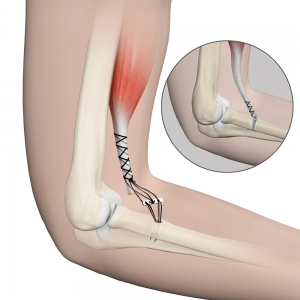

Distal Biceps Tendon Repair Distal Biceps Tendon Tear

Biceps Tendon Tear at the Elbow OrthoInfo AAOS outlet, What is a Biceps Tendon Rupture and How is it Fixed outlet, Ruptured Biceps or Triceps Tendon Golden State Orthopedics Spine outlet, Guide Physical Therapy Guide to Biceps Tendon Rupture Choose PT outlet, Distal biceps rupture outlet, Biceps Tendon Tear at the Elbow OrthoInfo AAOS outlet, Distal Biceps Avulsion Shoulder Elbow Orthobullets outlet, Biceps Tendon Rupture JETem outlet, Biceps Tendon Tear at the Shoulder OrthoInfo AAOS outlet, Dr Terence Moopanar Biceps tear outlet, Proximal Biceps Tendon Rupture Welwyn Garden City Shoulder outlet, Bicep Tendon Tear Info Florida Orthopaedic Institute outlet, Distal Biceps Tendon Tear Brandon P. Donnelly MD outlet, Torn Biceps Prevention and Treatment outlet, Popeye deformity associated with proximal biceps tendon rupture outlet, Biceps tendon rupture Wikipedia outlet, What is a Biceps Tendon Rupture and How is it Fixed outlet, Bicep Tendon Tear Info Florida Orthopaedic Institute outlet, Biceps Tendon Tear at the Elbow Dr. Groh outlet, What is Proximal Biceps Rupture How to Treat This Condition outlet, Biceps Tendon Tear at the Elbow Rehab My Patient outlet, Distal Biceps Tendon Problems Manhattan New York outlet, Biceps Tendon Tear Treatment Proximal Biceps Tear Distal outlet, The Hook Test Don t Miss A Rupture of the Biceps Tendon at the outlet, Biceps Ruptures Yorkshire Shoulder Clinic outlet, Distal Biceps Tendon Rupture Symptoms Treatment SportsMD outlet, What is a torn bicep tendon at the elbow OrthoIndy Blog outlet, Proximal Biceps Tenodesis Los Angeles Biceps Tendon Tear Anaheim outlet, Biceps Tendon Injury The Hand and Wrist Institute outlet, Proximal Biceps Tendon Rupture Popeye Deformity Everything You Need To Know Dr. Nabil Ebraheim outlet, Biceps Tendon Tear Mississauga and Oakville Chiropractor and outlet, Biceps Tendon Tear at the Shoulder Rehab My Patient outlet, Biceps Tendon Tear at the Elbow OrthoInfo AAOS outlet, Distal Biceps Tendon Repair Distal Biceps Tendon Tear outlet, Biceps Tendon Repair Advanced Orthopaedics Sports Medicine outlet.

Biceps Tendon Tear at the Elbow OrthoInfo AAOS outlet, What is a Biceps Tendon Rupture and How is it Fixed outlet, Ruptured Biceps or Triceps Tendon Golden State Orthopedics Spine outlet, Guide Physical Therapy Guide to Biceps Tendon Rupture Choose PT outlet, Distal biceps rupture outlet, Biceps Tendon Tear at the Elbow OrthoInfo AAOS outlet, Distal Biceps Avulsion Shoulder Elbow Orthobullets outlet, Biceps Tendon Rupture JETem outlet, Biceps Tendon Tear at the Shoulder OrthoInfo AAOS outlet, Dr Terence Moopanar Biceps tear outlet, Proximal Biceps Tendon Rupture Welwyn Garden City Shoulder outlet, Bicep Tendon Tear Info Florida Orthopaedic Institute outlet, Distal Biceps Tendon Tear Brandon P. Donnelly MD outlet, Torn Biceps Prevention and Treatment outlet, Popeye deformity associated with proximal biceps tendon rupture outlet, Biceps tendon rupture Wikipedia outlet, What is a Biceps Tendon Rupture and How is it Fixed outlet, Bicep Tendon Tear Info Florida Orthopaedic Institute outlet, Biceps Tendon Tear at the Elbow Dr. Groh outlet, What is Proximal Biceps Rupture How to Treat This Condition outlet, Biceps Tendon Tear at the Elbow Rehab My Patient outlet, Distal Biceps Tendon Problems Manhattan New York outlet, Biceps Tendon Tear Treatment Proximal Biceps Tear Distal outlet, The Hook Test Don t Miss A Rupture of the Biceps Tendon at the outlet, Biceps Ruptures Yorkshire Shoulder Clinic outlet, Distal Biceps Tendon Rupture Symptoms Treatment SportsMD outlet, What is a torn bicep tendon at the elbow OrthoIndy Blog outlet, Proximal Biceps Tenodesis Los Angeles Biceps Tendon Tear Anaheim outlet, Biceps Tendon Injury The Hand and Wrist Institute outlet, Proximal Biceps Tendon Rupture Popeye Deformity Everything You Need To Know Dr. Nabil Ebraheim outlet, Biceps Tendon Tear Mississauga and Oakville Chiropractor and outlet, Biceps Tendon Tear at the Shoulder Rehab My Patient outlet, Biceps Tendon Tear at the Elbow OrthoInfo AAOS outlet, Distal Biceps Tendon Repair Distal Biceps Tendon Tear outlet, Biceps Tendon Repair Advanced Orthopaedics Sports Medicine outlet.